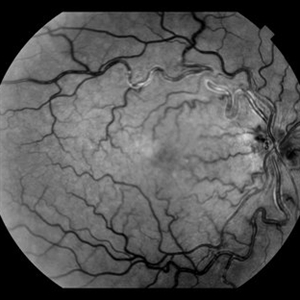

Sickle Cell Retinopathy with Sea Fans (angiogram)

Fluorescein angiography (mid phase) of a 40-year-old man with African heritage and sickle SC disease. Sea fans are present temporal to the macula.

Photographer: Geoffrey Emerson, MD, PhD, Retina Center, Minneapolis

Condition/keywords: sea fan, sickle cell retinopathy